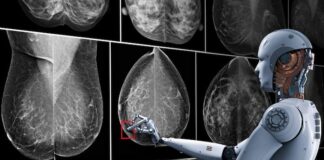

La Inteligencia Artificial permitirá avanzar hacia un tratamiento menos invasivo del...

Redacción Ciencia.- Un equipo de científicos ha creado una nueva herramienta basada en la inteligencia artificial (IA) que permite pronosticar con gran precisión la...